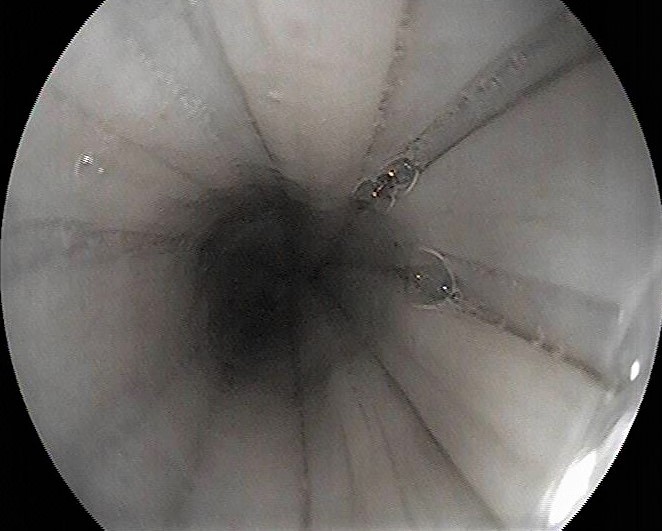

Die Endoskopische Untersuchung der Luftröhre und der Lunge

kann bei Symptomen, wie z.B. Husten, Leistungsabfall, verstärkte abdominale Atmung oder Atemgeräusche indiziert sein. Mit Hilfe der Tracheobronchoskopie ist die Adspektion der Schleimhaut der tiefen luftführenden Wege und deren pathologische Veränderungen möglich. Häufig sind Sekretansammlungen im Bereich der Luftröhre und Bronchien sichtbar, welche jeweils nach Probenentnahme für zytologische und mikrobiologische Untersuchungen zur Verfügung stehen. Nur hierdurch lässt sich das Equine Asthma und deren Unterformen, welche einer unterschiedlichen Therapie bedürfen, von anderen Atemwegserkrankungen differenzieren und zielgerichtet behandeln! Neben Sekretansammlungen in den luftführenden Wegen, sind auch Entzündungen, Ödeme, Fremdkörper oder Blutbeimengungen (z.B. beim belastungsinduzierten Lungenbluten) feststellbar.